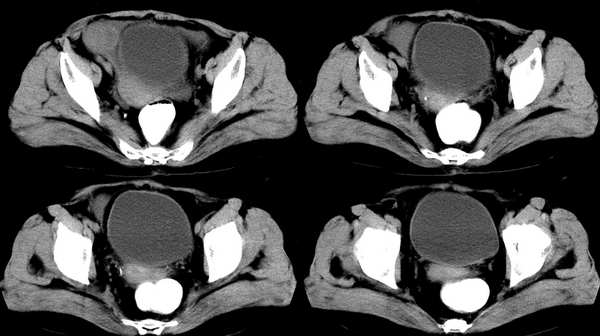

女,59岁,憋气、下腹不适一个月。胸透:双侧大量胸腔积液,反复抽胸水化验为漏出液。彩超示:盆腔占位

右侧卵巢区囊实性占位性病变,内见高密度及囊性脂肪密度,实性部分强化明显,囊性部分未见强化,结合病史多考虑:右侧卵巢恶性畸胎瘤。

右侧卵巢区囊实性占位性病变,内见高密度及囊性脂肪密度。考虑:右侧卵巢恶性畸胎瘤。